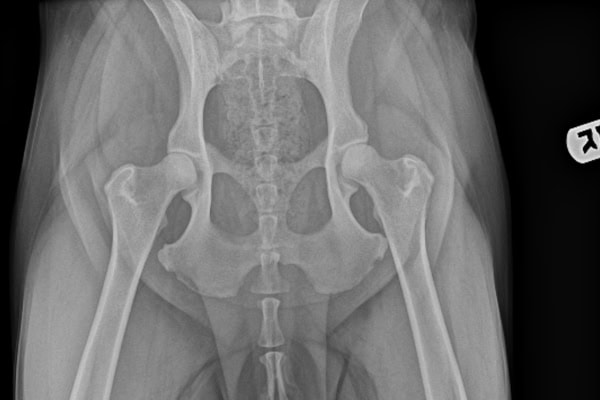

A number of conformational abnormalities make up hip dysplasia in dogs, including:

- A shallow acetabulum

- A flattened femoral head

- A thick femoral neck (the neck of the femur connects the head to the long part of the bone).

These issues can often be seen on X-rays of the hips.